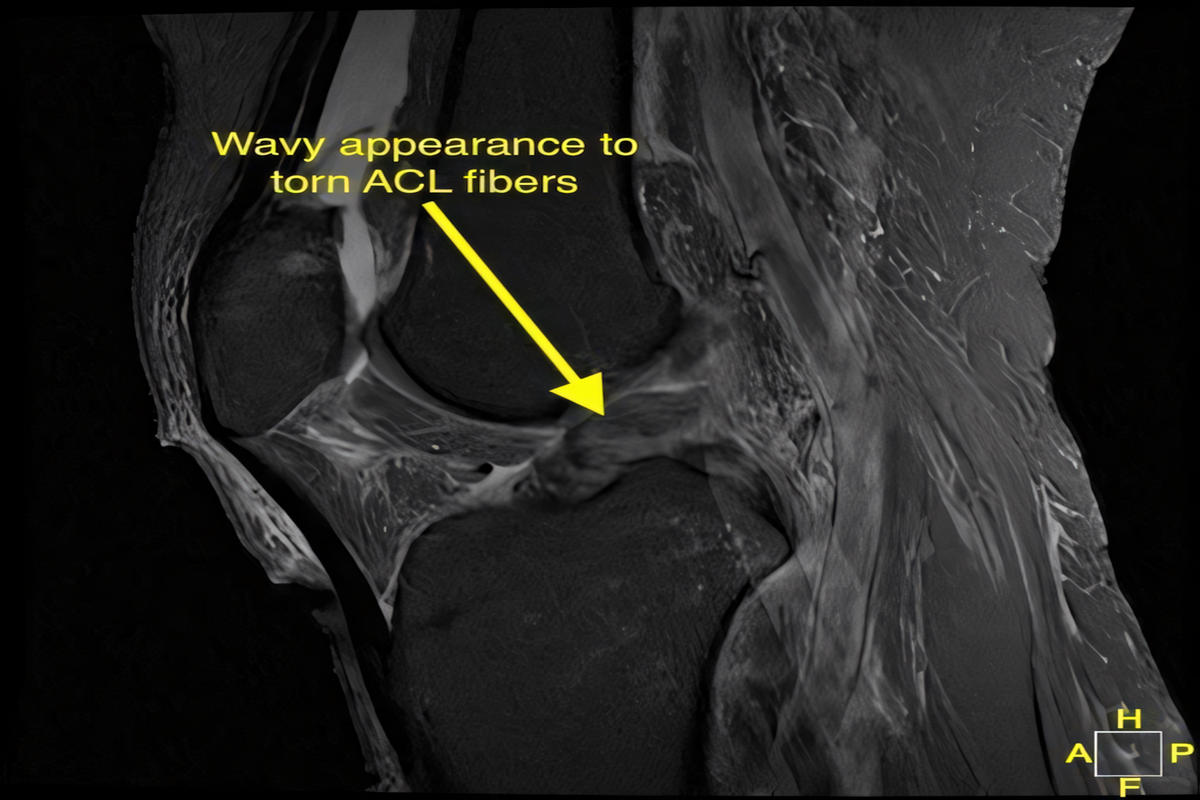

Ακτινογραφίες για αποκλεισμό οστικών κακώσεων

Μαγνητική τομογραφία (MRI), που επιβεβαιώνει τη ρήξη πρόσθιου χιαστού και αναδεικνύει συνοδές βλάβες σε μηνίσκους, χόνδρο ή πλάγιους συνδέσμους

Η MRI αποτελεί την εξέταση εκλογής για την τεκμηρίωση της βλάβης.